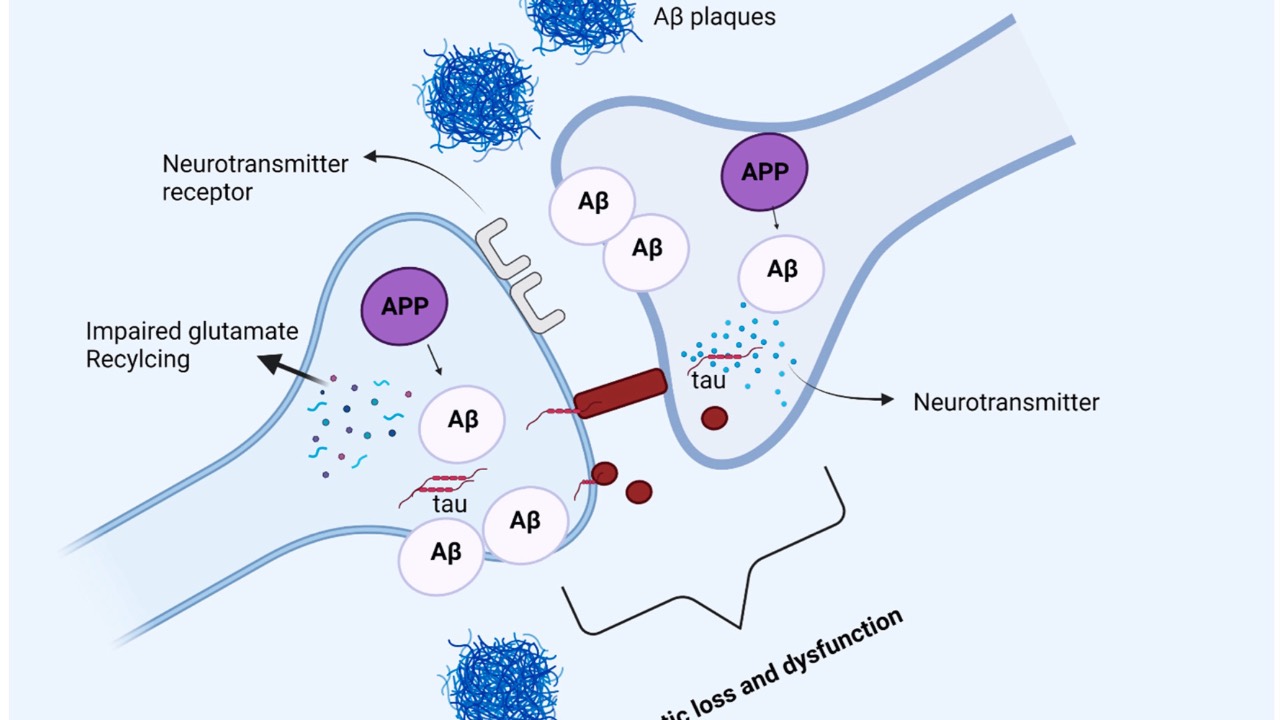

Glaucoma Treatment & Alzheimers' Risk

Recent findings published just today in Nature: Eye has uncovered a concerning link between certain glaucoma medications and Alzheimers' disease (AD) risk.

A nationwide cohort study in Taiwan found glaucoma patients using topical alpha-2 adrenergic agonists had a significantly higher risk of d...